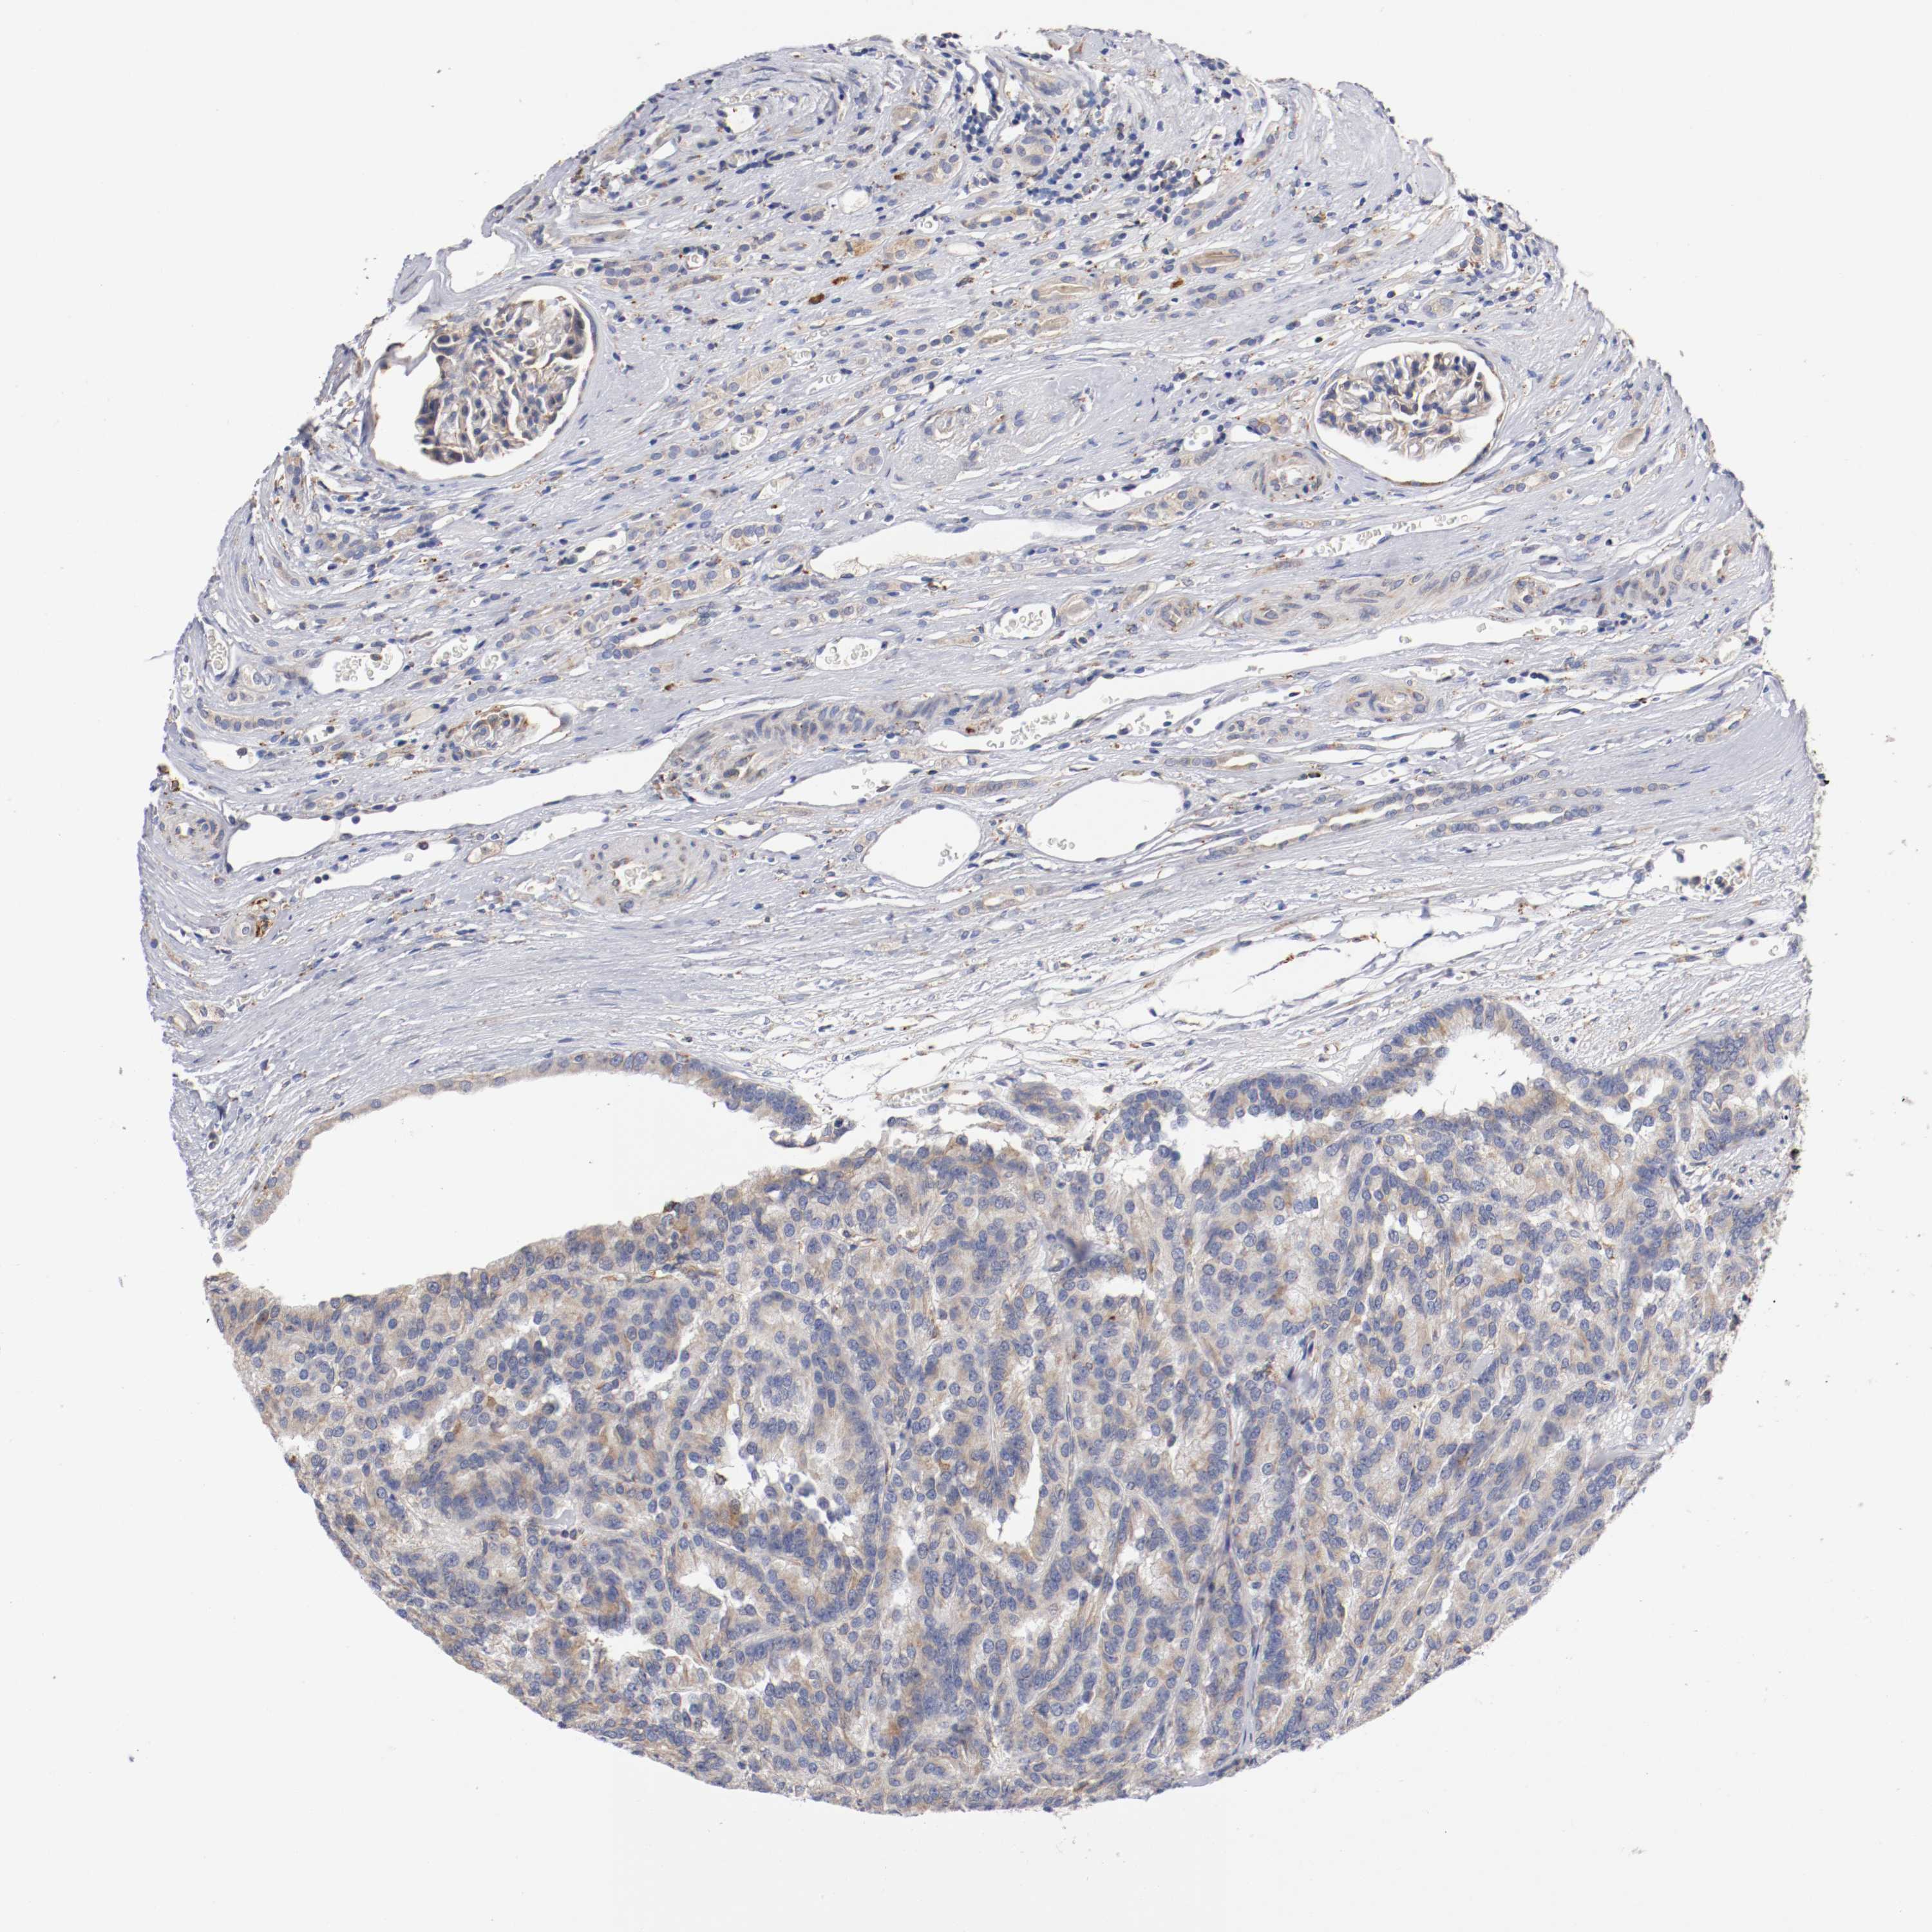

KIDNEY RENAL CLEAR CELL CARCINOMA (VALIDATION) - Interactive survival scatter ploti

The Survival Scatter plot shows the clinical status (i.e. dead or alive) for all individuals in the patient cohort, based on the same data that underlies the corresponding Kaplan-Meier plots. Patients that are alive at last time for follow-up are shown in blue and patients who have died during the study are shown in red.

The x-axis shows the expression levels (FPKM) of the investigated gene in the tumor tissue at the time of diagnosis. The y-axis shows the follow-up time after diagnosis (years). Both axes are complimented with kernel density curves demonstrating the data density over the axes. The top density plot shows the expression levels (FPKM) distribution among dead (red) and alive patients (blue). The right density plot shows the data density of the survived years of dead patients with high and low expression levels respectively, stratified using the cutoff indicated by the vertical dashed line through the Survival Scatter plot. This cutoff is automatically defined based on the FPKM cutoff that minimizes the p-score. The cutoff can be changed by dragging the vertical line or by entering a cutoff value in the square labeled "Current cut-off".

Under the Survival Scatter plot the p-score landscape (black curve; left axis) is shown together with dead median separation (red curve; right axis). Dead median separation is the difference in median mRNA expression between patients who have died with high and low expression, respectively. It is calculated as follows: median FPKM expression of dead patients with high expression - median FPKM expression of dead patients with low expression. This is intended to aid the user in visually exploring custom cutoffs and the associated p-scores and dead median separation.

Individual patient data is displayed and can be filtered by clicking on one or more of the category buttons on the top of the page. Categories describing expression level and patient information include: high, low, alive, dead, female, male and tumor stages. The scale of the x-axis can be toggled between linear and log-scale by clicking on the "x log" button. Mouse-over function shows TCGA ID, patient information and mRNA expression (FPKM) for each patient.

& Survival analysisi

Kaplan-Meier plots summarize results from analysis of correlation between mRNA expression level and patient survival. Patients were divided based on level of expression into one of the two groups "low" (under cut off) or "high" (over cut off). X-axis shows time for survival (years) and y-axis shows the probability of survival, where 1.0 corresponds to 100 percent.

TRAF2 is not prognostic in Kidney Renal Clear Cell Carcinoma (validation)

Best expression cut offi

Based on the FPKM value of each gene, patients were classified into two groups and association between prognosis (survival) and gene expression (FPKM) was examined. The best expression cut-off refers the FPKM value that yields maximal difference with regard to survival between the two groups at the lowest log-rank P-value. Best expression cut-off was selected based on survival analysis .

When clicking on this number, the vertical dashed line indicating cut-off, the interactive survival plot, and the Kaplan-Meier curve will be adjusted to show results based on the best expression cut-off.

: 13.68

Median expressioni

Median expression refers to the median FPKM value calculated based on the gene expression (FPKM) data from all patients in this dataset. When clicking on this number, the vertical dashed line indicating cut-off, the interactive survival plot, and the Kaplan-Meier curve will be adjusted to show results based on the median expression.

: N/A

Median follow up timei

Median follow up time refers to the median time (years) after diagnosis with this type of cancer, based on clinical data from all patients in this dataset.

P scorei

Log-rank P value for Kaplan-Meier plot showing results from analysis of correlation between mRNA expression level and patient survival.

N/A

5-year survival highi

5-year survival for patients with higher expression than the expression cutoff.

For melanoma and glioma, 3-year survival is shown.

5-year survival lowi

5-year survival for patients with lower expression than the expression cutoff.

TCGA RNA samplesi

RNA-seq data is reported as average FPKM (number Fragments Per Kilobase of exon per Million reads), generated by the The Cancer Genome Atlas (TCGA) .

Normal distribution across the dataset is visualized with box plots, shown as median and 25th and 75th percentiles. Points are displayed as outliers if they are above or below 1.5 times the interquartile range. FPKM values of the individual samples are presented next to the box plot.

Average pTPM 17.4

Number of samples 100